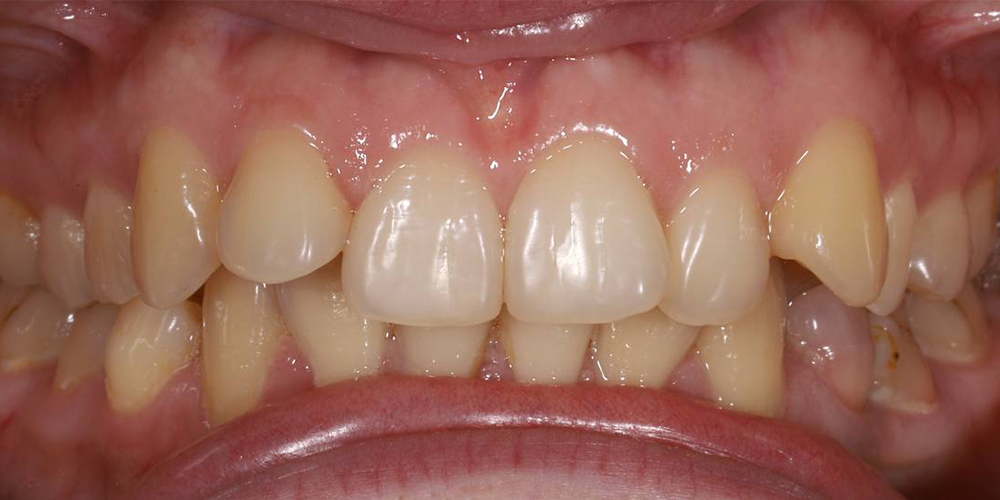

Коррекция прикуса и выравнивание зубов в подростковом возрасте